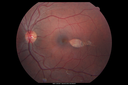

Coats' Disease - 14 year old - Asymptomatic470 viewsPresented with macular exudates. Temporal macroaneurysms responded to laser. Ultra-wide field FA shows nonperfusionNov 07, 2016